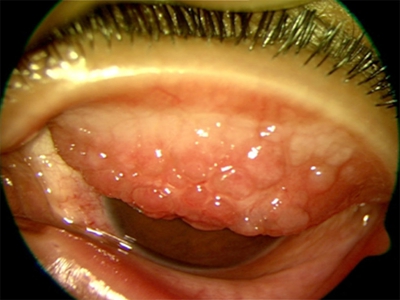

特应性角结膜炎眼皮里有密密麻麻小疙瘩图

特应性角结膜炎患者翻开眼皮可见铺路石样的密密麻麻的小疙瘩,直径均>1mm,疙瘩间眼结膜泛白肿起,此时进行眼睑冷敷可暂时缓解眼部的不适感,还应及时就医正确用药。